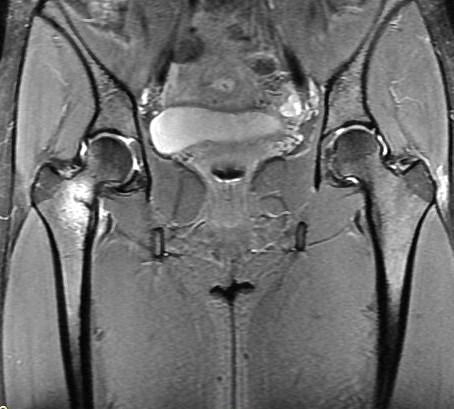

Figure 3 for case Calcar stress fracture ( RID4695 )

Figure 3